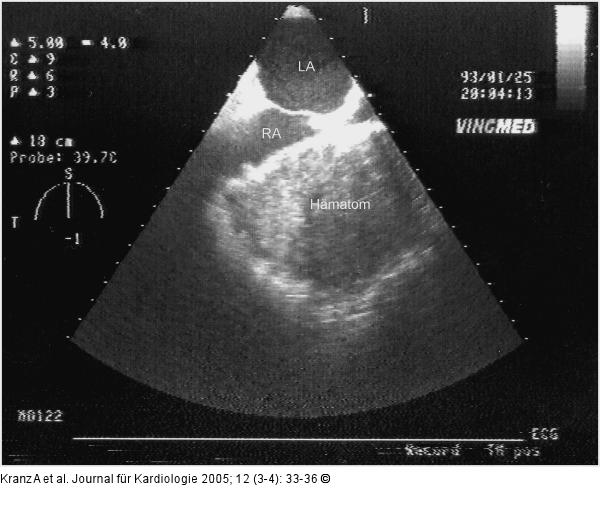

Abbildung 10a-b: Postoperative Veränderungen |

Abbildung 10b

Abbildung 10a-b: Postoperative Veränderungen